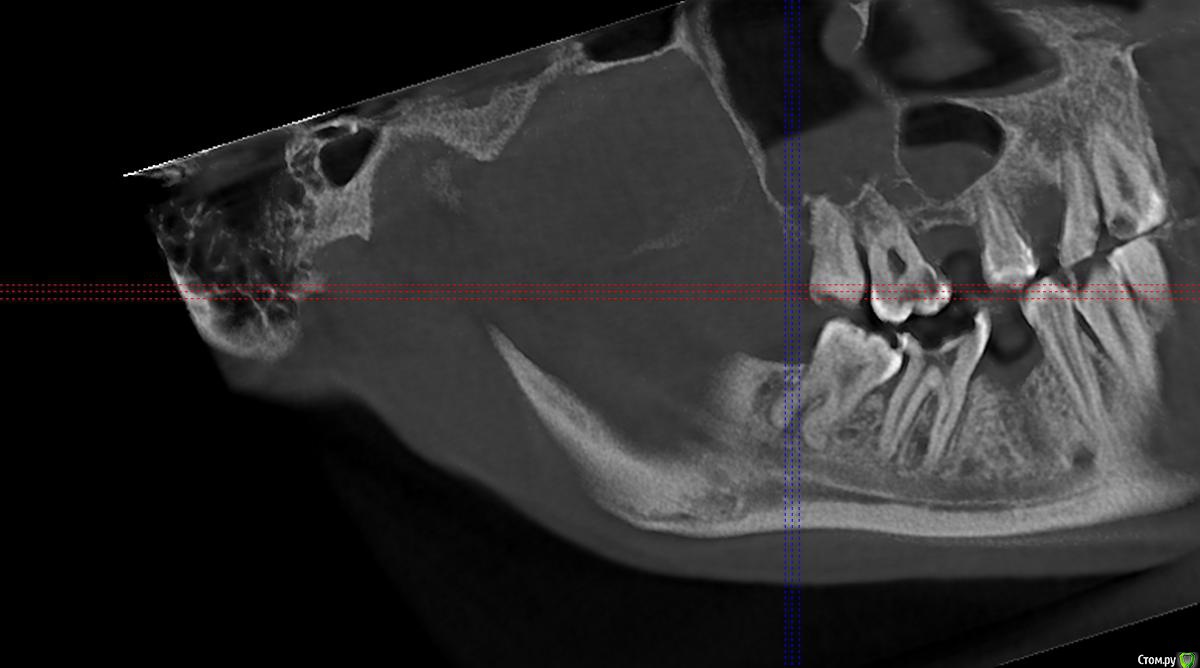

carloss Опубликовано 2 февраля, 2016 Поделиться Опубликовано 2 февраля, 2016 попробуйте выложить срезы КТ той области, где удаляли зуб Ссылка на комментарий

erm Опубликовано 2 февраля, 2016 Автор Поделиться Опубликовано 2 февраля, 2016 попробуйте выложить срезы КТ той области, где удаляли зубвот не знаю оно или нет Ссылка на комментарий

carloss Опубликовано 2 февраля, 2016 Поделиться Опубликовано 2 февраля, 2016 (изменено) по этим срезам вроде все нормально.. попробуйте еще несколько таких же, чуть спереди и сзади.. пытаюсь скачать вашу КТ, не получается у меня открыть Изменено 2 февраля, 2016 пользователем carloss Ссылка на комментарий

carloss Опубликовано 2 февраля, 2016 Поделиться Опубликовано 2 февраля, 2016 Вы там выложили два среза, больше нет? Хотя бы еще парочку чуть спереди сзади Ссылка на комментарий

carloss Опубликовано 2 февраля, 2016 Поделиться Опубликовано 2 февраля, 2016 (изменено) если у кого получилось открыть КТ, выложите плз пару срезов в проекции ментального отверстия Изменено 2 февраля, 2016 пользователем carloss 1 Ссылка на комментарий

St. Опубликовано 3 февраля, 2016 Поделиться Опубликовано 3 февраля, 2016 Вот скрины области 34-37 http://s017.radikal.ru/i422/1602/29/827509a5e8b7.jpghttp://s020.radikal.ru/i715/1602/79/8ae3b175009f.jpghttp://s019.radikal.ru/i642/1602/df/6069a3f8c407.jpghttp://s020.radikal.ru/i708/1602/27/32fb4607230f.jpghttp://s019.radikal.ru/i618/1602/5b/21d7f2ba2d62.jpghttp://s019.radikal.ru/i619/1602/de/2eb04456028f.jpghttp://s010.radikal.ru/i311/1602/bd/f4a561bc6c1f.jpghttp://s017.radikal.ru/i414/1602/57/97d820fac3da.jpg Ссылка на комментарий